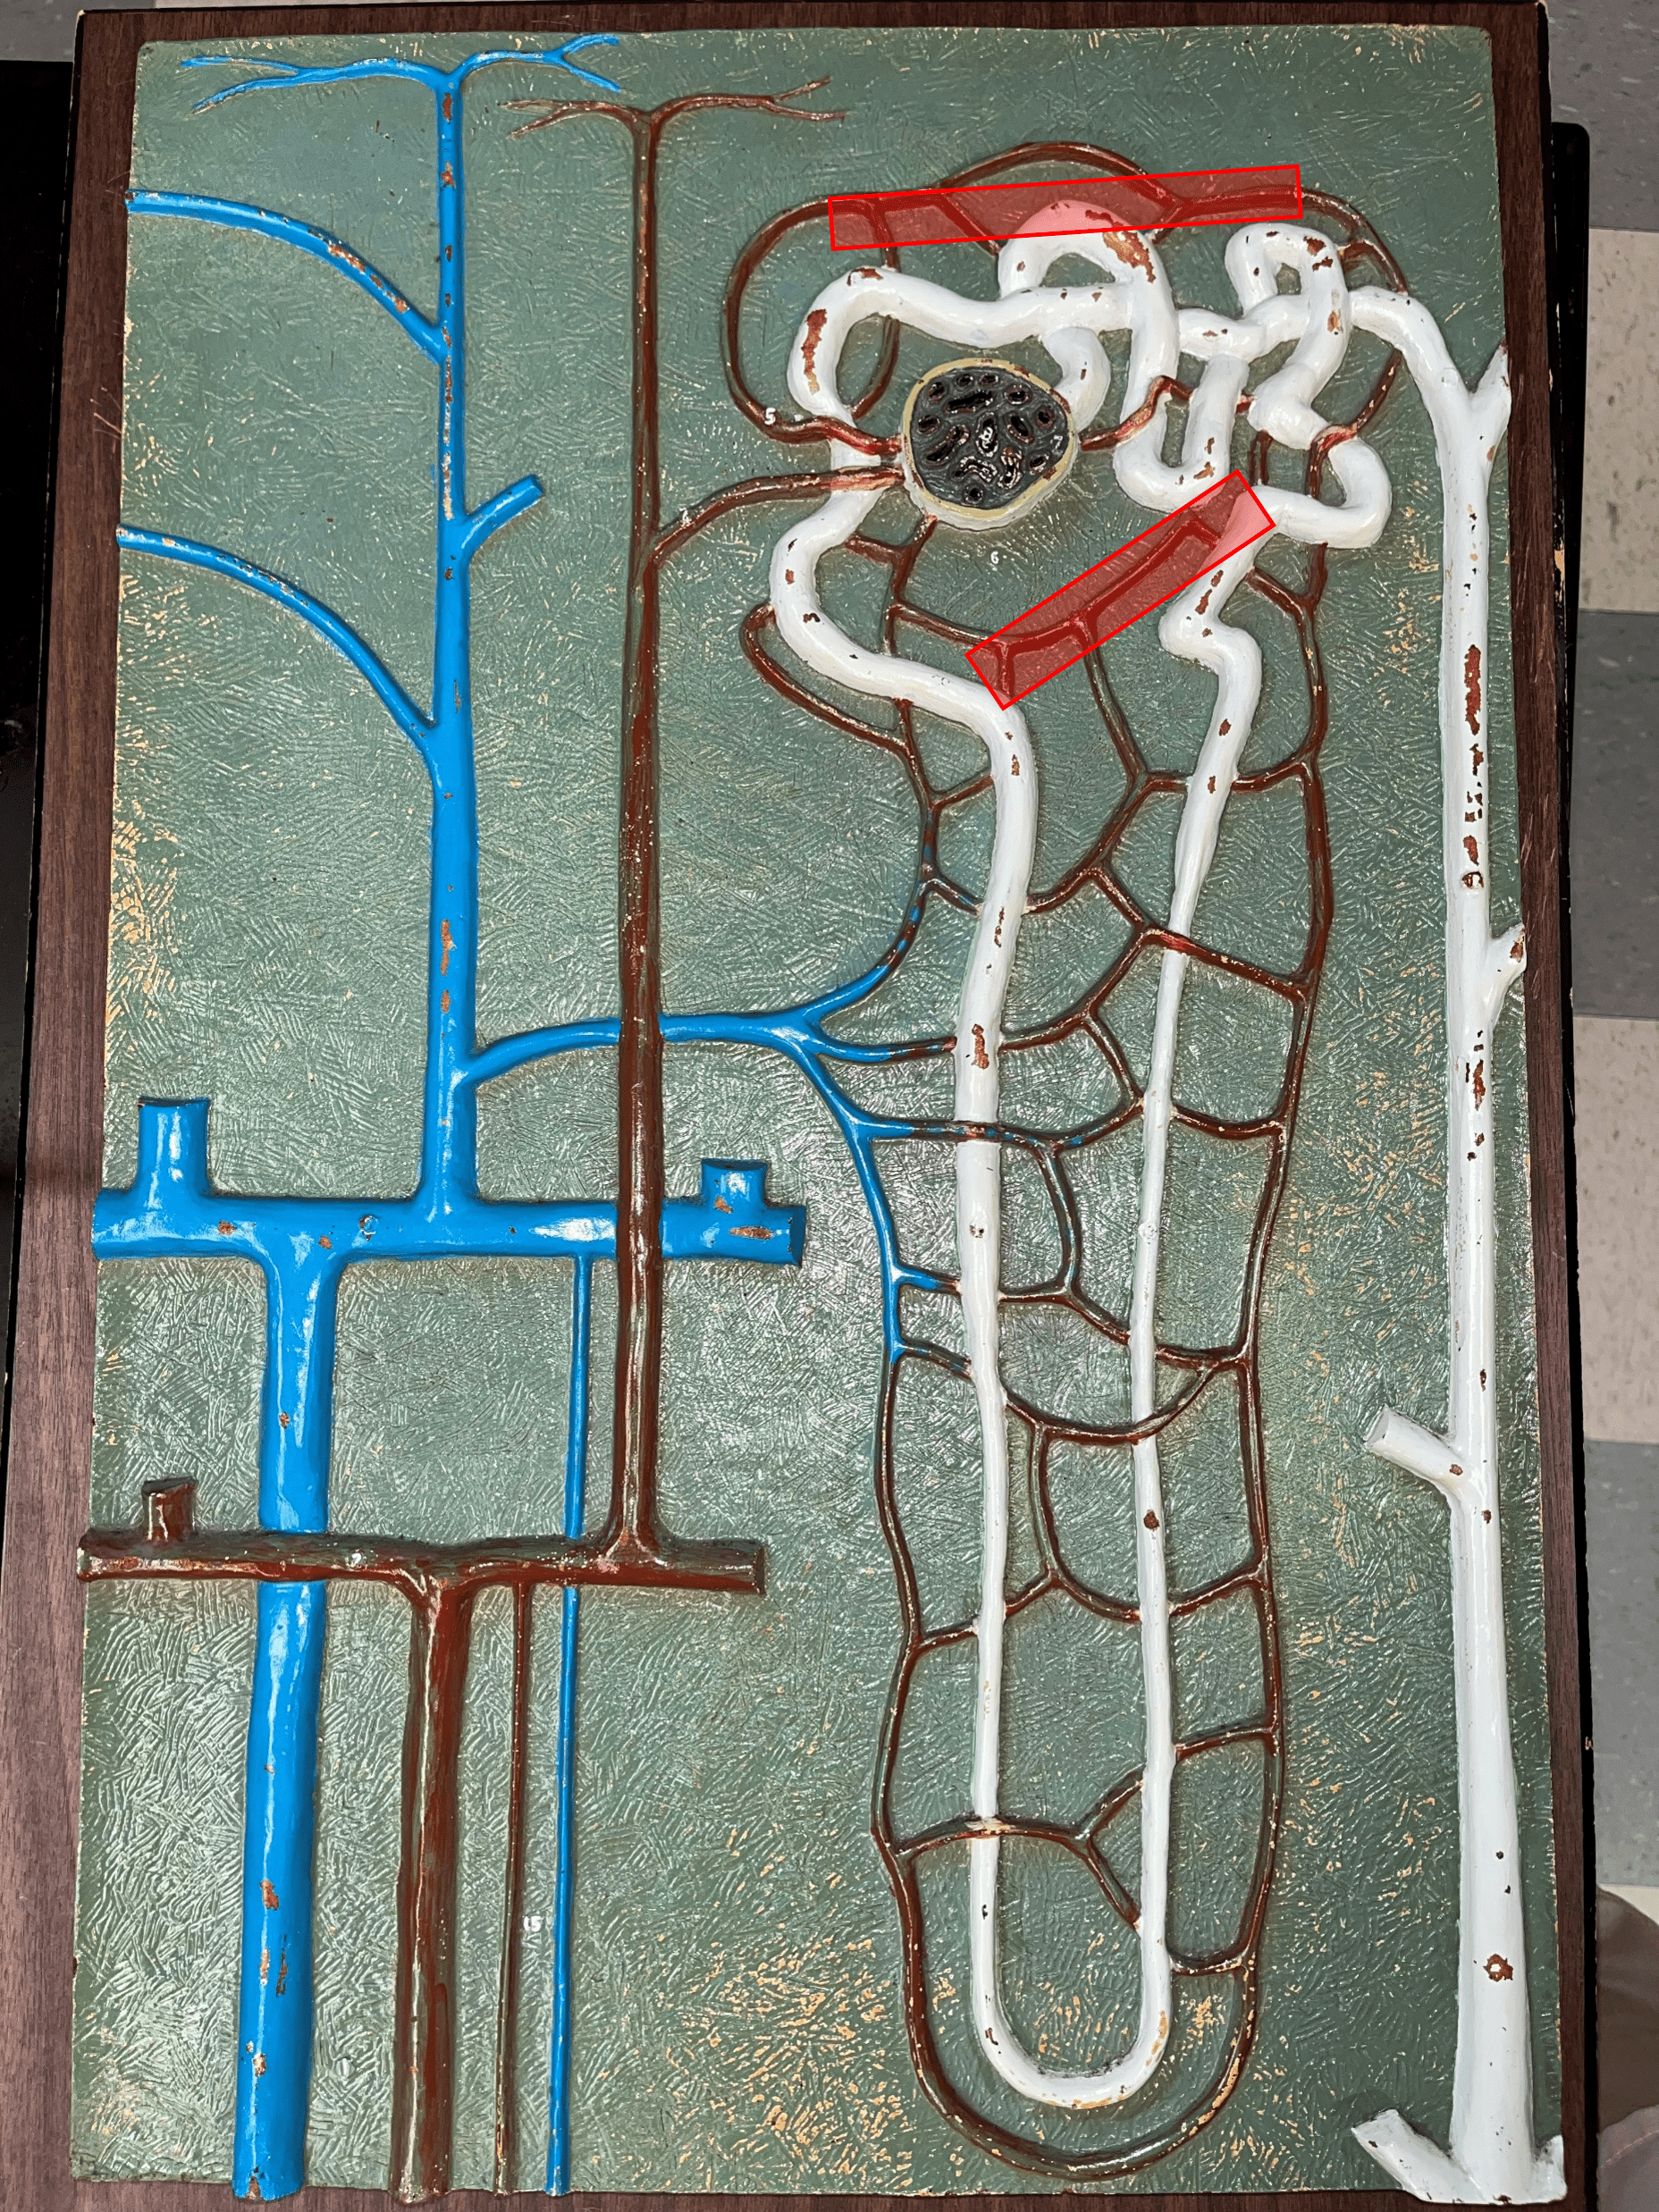

nephron

• The functional subunit of the kidney.

• Site of urine formation and renal function.

• Composed of a renal corpuscle and a renal tubule.

• Site of urine formation and renal function.

• Composed of a renal corpuscle and a renal tubule.

renal corpuscle

• Part of a nephron.

• Filters blood.

• Composed of a glomerulus enclosed within a glomerular capsule.

• Filters blood.

• Composed of a glomerulus enclosed within a glomerular capsule.

41

glomerulus

• Slide histology of the nephron.

• Part of a renal corpuscle.

• The capillary network of a renal corpuscle.

• Part of a renal corpuscle.

• The capillary network of a renal corpuscle.

42

renal tubule

• Slide histology of the nephron.

• Part of a nephron.

• Modifies glomerular filtrate by reabsorption and secretion of water and ions.

• Divided into the proximal convoluted tubule, loop of Henle, and distal convoluted tubule.

• Part of a nephron.

• Modifies glomerular filtrate by reabsorption and secretion of water and ions.

• Divided into the proximal convoluted tubule, loop of Henle, and distal convoluted tubule.

48

proximal convoluted tubule

• The first part of a renal tubule.

• Primary site of water and solute reabsorption.

• Begins immediately after the renal corpuscle.

• Abbreviated PCT.

• Primary site of water and solute reabsorption.

• Begins immediately after the renal corpuscle.

• Abbreviated PCT.

49

descending limb

• The proximal second part of a renal tubule.

• Part of the loop of Henle.

• Permeable to water but not solutes.

• Part of the loop of Henle.

• Permeable to water but not solutes.

50

ascending limb

• The distal second part of a renal tubule.

• Part of the loop of Henle.

• Permeable to solutes but not water.

• Part of the loop of Henle.

• Permeable to solutes but not water.

51

distal convoluted tubule

• The third part of a renal tubule.

• Primary site of secretion of excess solutes.

• Abbreviated DCT.

• Primary site of secretion of excess solutes.

• Abbreviated DCT.

52

collecting duct

• The convergence of several distal convoluted tubules.

• Descends through the renal pyramid.

• Merges with others to form larger papillary ducts that drain into the minor calyces.

• Abbreviated CD.

• Descends through the renal pyramid.

• Merges with others to form larger papillary ducts that drain into the minor calyces.

• Abbreviated CD.

53

afferent arteriole

• Branches of an interlobular artery.

• Supplies the glomerulus of a nephron for blood filtration.

• Supplies the glomerulus of a nephron for blood filtration.

efferent arteriole

Vessel carrying blood away from the glomerulus to the peritubular capillaries.

peritubular capillaries

• Branches of an efferent arteriole.

• Supplies the adjacent renal tubules in the renal cortex.

• Supplies the adjacent renal tubules in the renal cortex.

vasa recta

• Branches of an efferent arteriole.

• Supplies the loops of Henle in the renal medulla.

• Supplies the loops of Henle in the renal medulla.